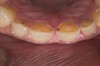

Figure 14  Postoperative smile.

Figure 14

White enamel shade was placed on the putty index and carried to the palatal surface of No. 9. This layer was spread uniformly and thinned out and spread along the entire width of the tooth (Figure 11). After curing this layer, A2 dentin was layered to simulate the lobular pattern seen in dentin of the natural teeth (Figure 12). After curing, a layer of transparent resin was placed in the incisal areas between the dentinal lobes. The final layer of A2 enamel was built and shaped to full contour (Figure 13). A similar build-up was done for all the remaining anterior teeth. The bite in MIP was adjusted such that there was uniform contact on all anterior teeth. The anterior guidance was harmonized to maintain uniformity in the contact of the incisors during protrusion and the canines and incisors during lateral excursions. Finishing and polishing was done per protocol (Figure 14 through Figure 18).13